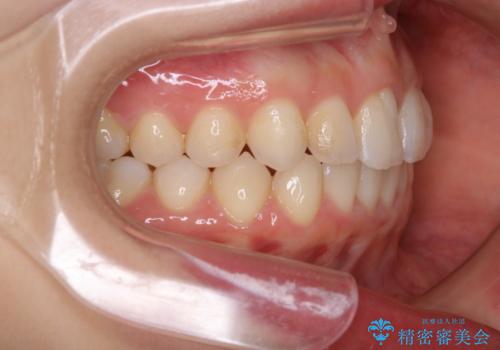

動きづらい前歯のねじれもマウスピース(インビザライン)で改善

- 前から2番目の歯が捻じれていることが気になるとご相談にいらした方です。

インビザラインFULLで治療を行いました。

上の前から2番目の歯は、一般的に周囲の歯と比べて小さく、動きづらい歯であると言われています。前歯にゴムかけを行うことで理想的な位置まで歯を動かしてくることが出来ました。